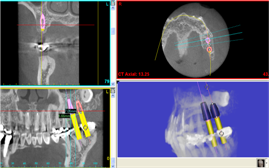

骨再生

骨再生した箇所にインプラントを埋入します。

CTで治療計画を綿密に練ったうえで行いました。

インプラント埋入の際の動画です。

画像をクリックすると、youtubeにジャンプします。

インプラント埋入

インプラント埋入後のレントゲン画像です。